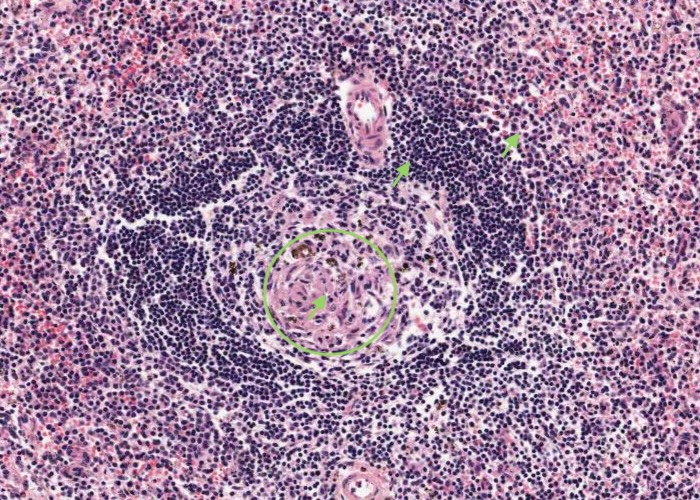

Look at a lymphatic nodule in the cortex. Identify a germinal centre and the corona (mantle) around it.

Look at the nodules in the cortex. Identify a germinal centre and the corona (mantle) around it. Most of the cells in the corona are small lymphocytes. In contrast, many of the cells in a germinal centre of the nodule have large, pale nuclei. This is why a germinal centre stains palely.

The maximal magnification is barely adequate. Scan the cortex for a germinal centre in which the cells are not jammed too heavily on top of one another.

If you see a large, pale nucleus which seems to have no cytoplasm at all around it then it is most likely a follicular dendritic cell. These cells actually have a lot of cytoplasm but it is stretched out into long arms that extend out of the plane of section. Their function is to hold antigen molecules on their surface and "present" them to lymphocytes. They are one type of antigen presenting cell. Various other cell types also present foreign or self antigens.

More rarely you will see nuclei as large as those of dendritic cells, but darker and with a discrete rim of basophilic cytoplasm. The cytoplasm will have a sharp outer perimeter. These cells are lymphoblasts. Their edges are visible because they do not have cytoplasmic arms sticking out.

Small lymphocytes dominate the corona. You can also find occasional prolymphocytes, with more, basophilic cytoplasm than small lymphocytes and with larger, paler nuclei. The supporting reticular cells have elongate nuclei. You also may come across a plasma cell or two.